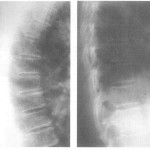

Кроме того, своевременно выявленное заболевание – это гарантия качественного лечения, направленного на полное восстановление организма, что в случае запущенности заболевания уже станет невозможным. На рентген снимке можно просмотреть заболевание уже на ранней стадии, что визуально при осмотре не будет определяться.